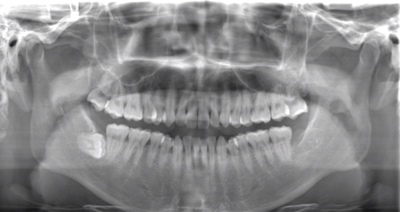

CASE 2

| 年齢・性別 | 30代・男性 |

| 主訴 | 左上下親知らず抜きたい |

| 抜歯期間 | 30分 |

| 抜歯費用 | 約2,500円(保険内) 別途CT撮影で3,000円 |

| 抜歯内容 | 左上下の親知らず抜歯 |